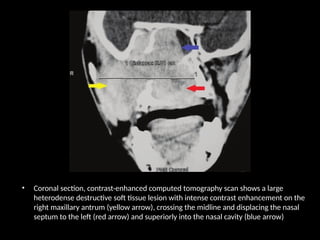

• Coronal section, contrast-enhanced computed tomography scan shows a large

heterodense destructive soft tissue lesion with intense contrast enhancement on the

right maxillary antrum (yellow arrow), crossing the midline and displacing the nasal

septum to the left (red arrow) and superiorly into the nasal cavity (blue arrow)

• contrast-enhanced computed tomography scan shows a large heterodense destructive soft

tissue lesion seen in the superior postero-lateral wall of the right nasal cavity, extending

into the nasopharynx and adjacent pterygopalatine fossa, right pre-maxillary space causing

bowing of the posterior antral wall: The characteristic Holman Miller sign (yellow arrow)

with erosion/ destruction of adjacent bones.